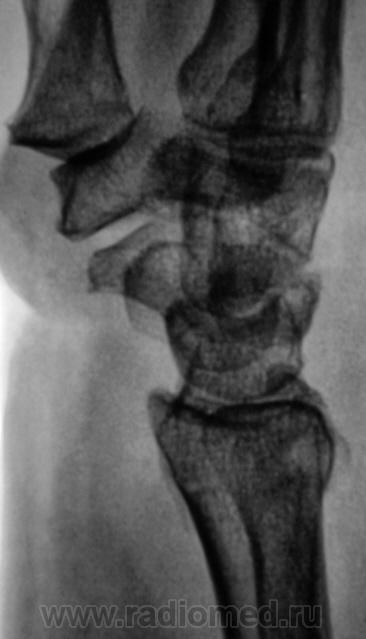

Травма.   Пациент направлен на рентгенографию лучезапястного сустава.